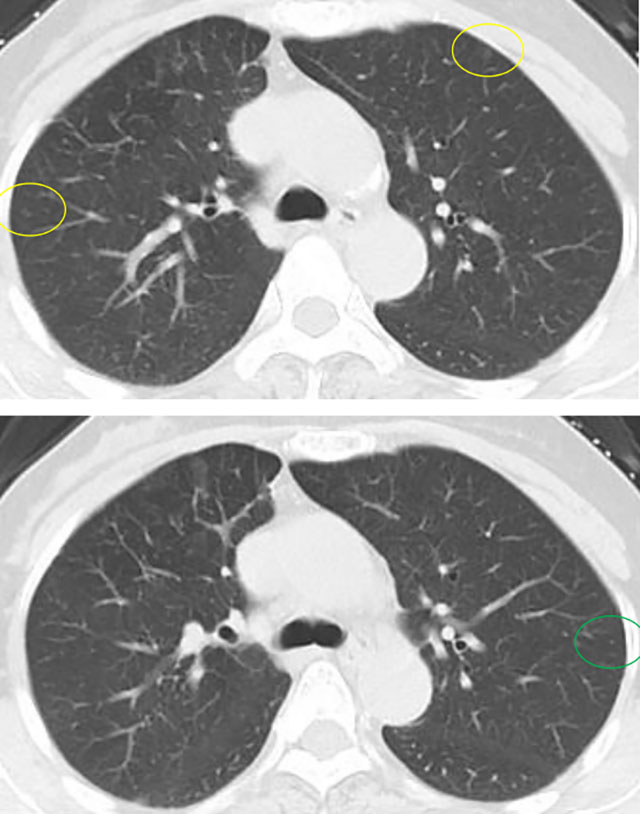

近期,阿姨复查影像展示与分析,1mm层薄层。

与术前及每年复查片对比,阿姨双肺多发磨玻璃结节,均未见显著改变,左肺上叶前段主病灶亦如此,密度很纯,未见增大及实性成分出现,术后5年虽可见血管弯曲,进展极慢,风险还是相对较低,且右肺上叶已经全切除。双肺多发相对较小磨玻璃密度结节,并且进展极慢、仍纯磨密度。该病灶目前没有必须到手术干预程度,只需6-12月复查随访,若有进展并要有风险增加时再考虑干预处理。